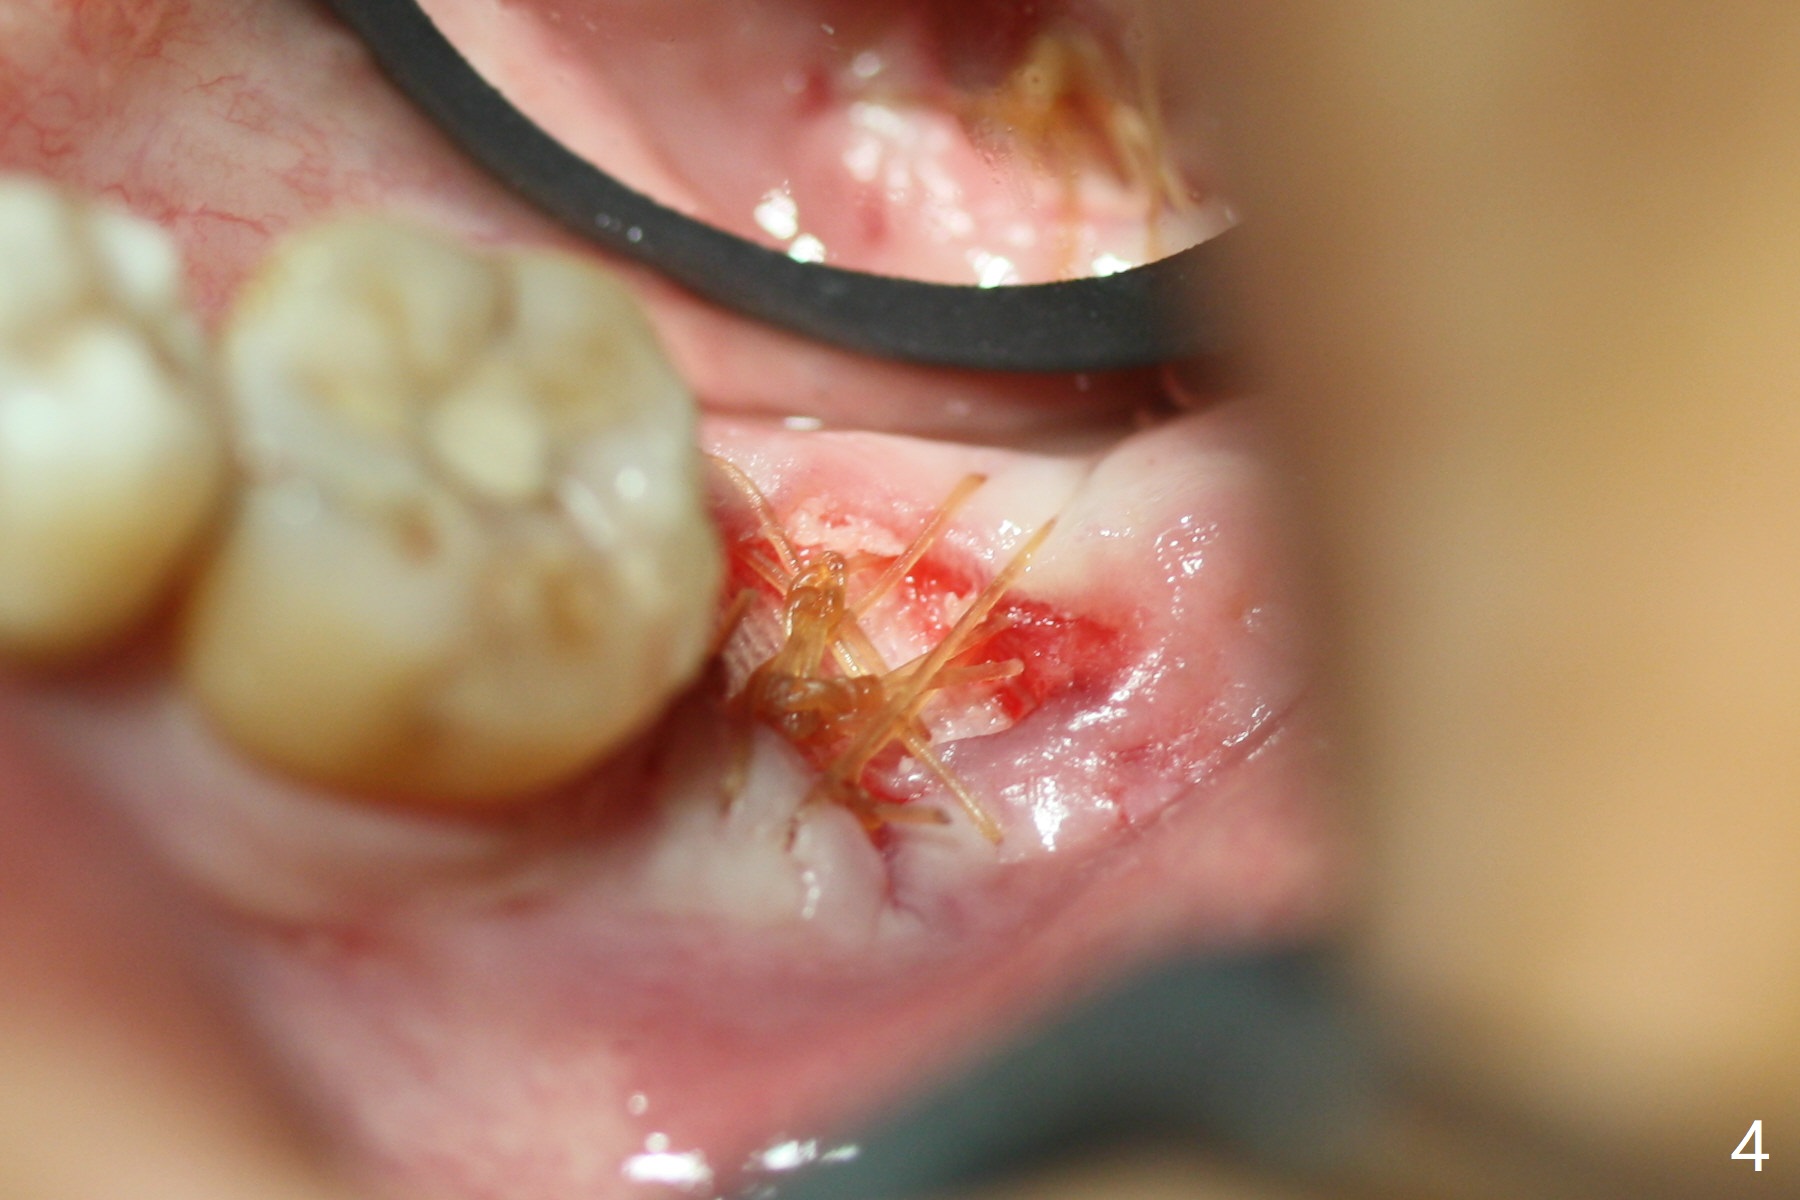

The patient with chronic buccal abscess at #31 is nervous.  After extraction, a 7x11 mm tapered implant drops into the single socket, which is close to the Inferior Alveolar Canal (Fig.2).  The bottom of the socket is sensitive to manipulation (explorer) after infiltration anesthesia.  A 8x14 mm tapered tap is placed without binding, neither is a 8x14 mm cylindrical implant.  The implant stability does not increase when Vera (.2-1.0 mm) or Vanilla (.5-1.0 mm) Graft is placed.  Socket preservation is finished with Collagen plug and 6-month membrane (Fig.3,4).